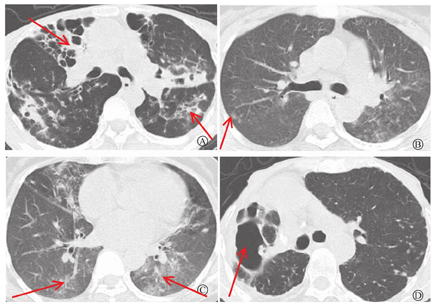

本组35例患者胸部影像学表现为支气管扩张10例(图1A),树芽征2例(图1B),肺部结节5例(图1B),肺部实变3例(图1C),空洞15例(图1D)。

注:A.两上肺均可见支气管扩张;B.右上叶后段可见树芽征;C.左下肺实变影,右下肺散在结节影;D.右上方肺空洞影